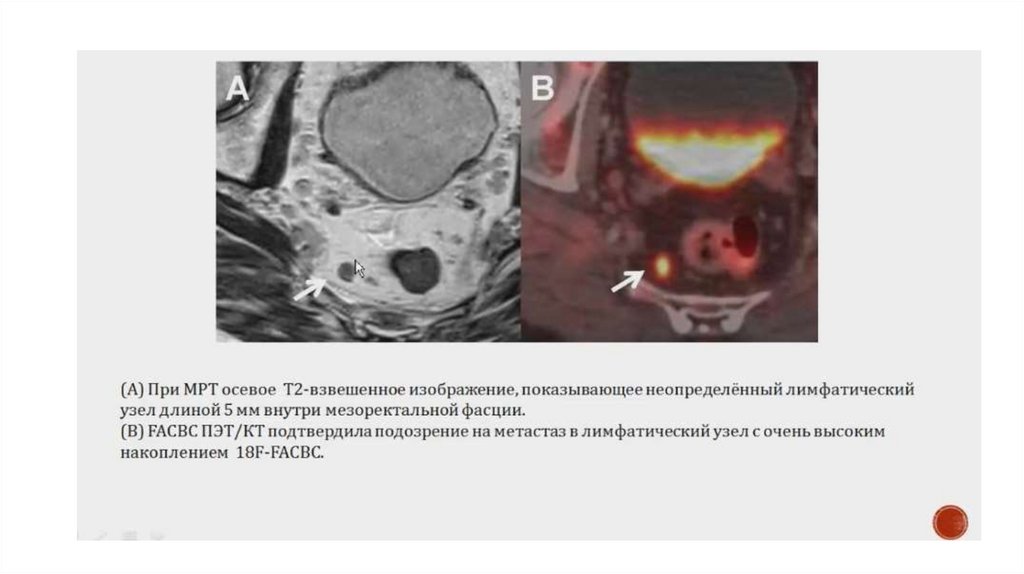

После узи мрт можно делать только после 11.5 мес. (поэтому лучше до сделать)